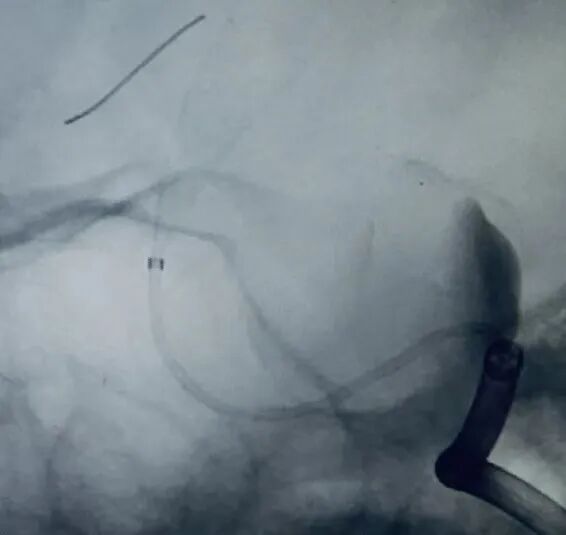

1、以Seldinger技术穿刺右侧股动脉成功后,留置6F股动脉鞘。6F DA导管超选至右侧颈内动脉海绵窦段,行3D造影提示:右侧颈内动脉床突段分叶状动脉瘤,载瘤动脉无严重迂曲,未见合并载瘤动脉严重狭窄,未见严重的脑血管痉挛。2、选择最佳工作角度,路图下用微导丝辅助支架0.027"微导管超选至右侧大脑中动脉,通过支架微导管释放一枚5.0*35mm抗凝血流导向密网支架(纽创医疗)。3、抗凝血流导向密网支架放置合适位置,完全覆盖瘤颈,释放后抗凝血流导向密网支架打开良好。术后造影见动脉瘤瘤体造影剂滞留明显,动脉瘤瘤颈造影剂滞留明显,靶动脉瘤Raymond Ⅲ级。